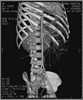

患儿,男,4岁,发现腹部包块1年余。查体:腹膨隆,可及约10 cm×10 cm大小包块,质软,无压痛。CT检查显示:腹腔内有略低密度占位性病变,约6.7 cm×16.7 cm×15.7 cm,密度均匀,腹部肠管受压向左前上腹移位(图1)。病变强化不明显,内见散在血管断面;肠系膜上动脉受压抬高,分支分散(图2)。肿物内可见沿肠系膜走行的血管影。诊断为腹腔内囊性占位——肠系膜淋巴管瘤不除外。

图1 CT平扫显示:腹腔内巨大略分叶占位性病变,密度比较均匀(白箭头),外周环以含气肠管(←)